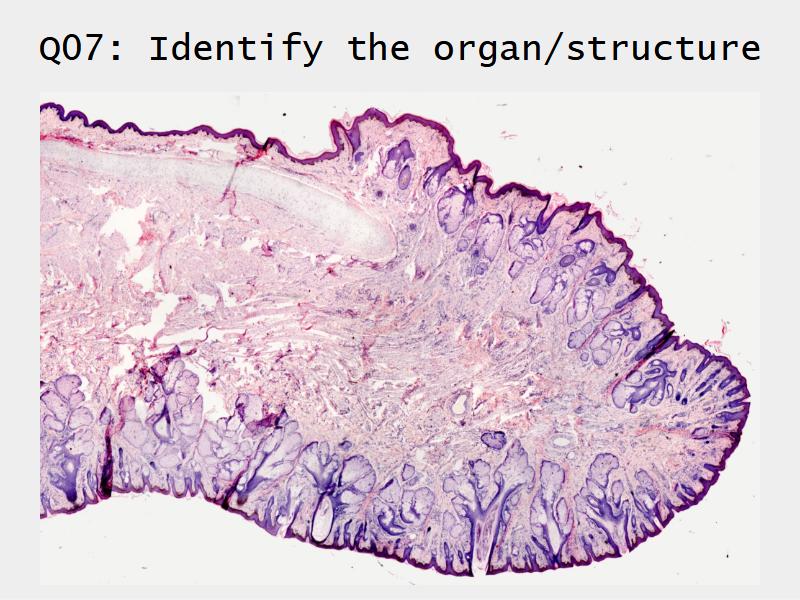

Respiratory System

Slides: Respiratory System

- Slide 71: Nostril

Nostril